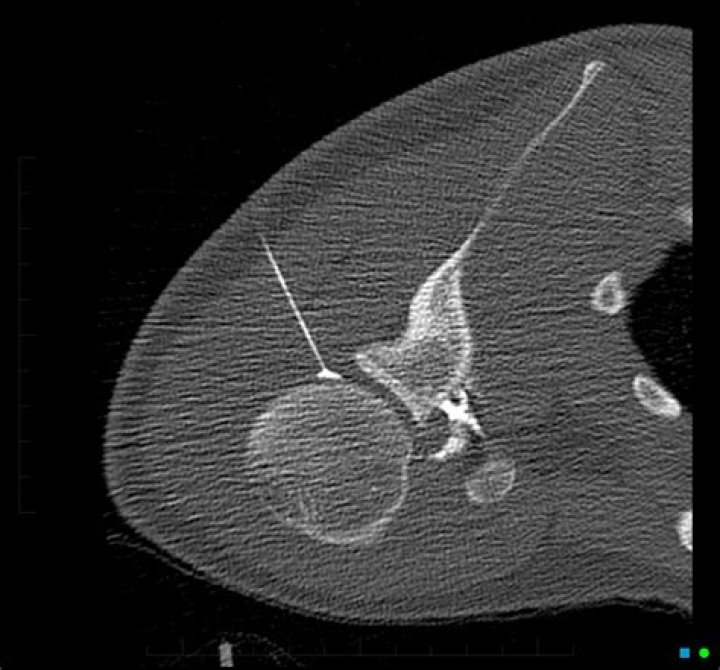

An arthrogram is performed to evaluate the structure and function of extremity joints, such as the shoulder, elbow, wrist, hip, knee or ankle. The procedure can help determine the need for treatment, including surgery or joint replacement.

An arthrogram provides a clear image of the soft tissue in the joint (e.g. ligaments and cartilage) so that a more accurate diagnosis about an injury or cause of a symptom, such as joint pain or swelling, can be made.

Is an arthrogram the same as an MRI?

An Arthrogram uses fluoroscopy and an MRI to specifically diagnoses injuries in the joint structures that an MRI alone would likely miss. MRIs can be ordered with contrast that is delivered intravenously, while an Arthrogram has contrast needle-guided directly into the injured joint.